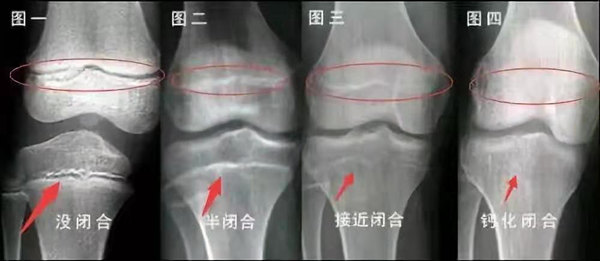

我們都知道,人體的高矮是由骨骼的生長(zhǎng)發(fā)育決定的,特別是下肢長(zhǎng)骨。長(zhǎng)骨呈長(zhǎng)管狀,在長(zhǎng)骨的兩端有一種專管骨骼生長(zhǎng)的骺軟骨,它與干骺端之間有一盤狀軟骨結(jié)構(gòu)稱為骺板(線),在幼兒的X光片上表現(xiàn)為一條較寬的透光帶。 (見下圖)

未成年時(shí)隨著年齡的增加骺軟骨端不斷骨化,骨骼就不斷增長(zhǎng)。當(dāng)骨骺線完全閉合時(shí)骨骼就停止生長(zhǎng),個(gè)子也就不再增長(zhǎng)了。一般骨骺端完全閉合的年齡是18~20歲左右。

青少年一般什么時(shí)候骨骺閉合?

一般女孩是在16歲,男孩是在18歲。

一般來說,女孩的骨齡超過14歲,男孩的骨齡超過16歲,這時(shí)其骨骺線已接近閉合,基本沒有長(zhǎng)高的機(jī)會(huì)了。

因此,越早了解骨骺線閉合情況,越早干預(yù),孩子長(zhǎng)高的可能性越大。